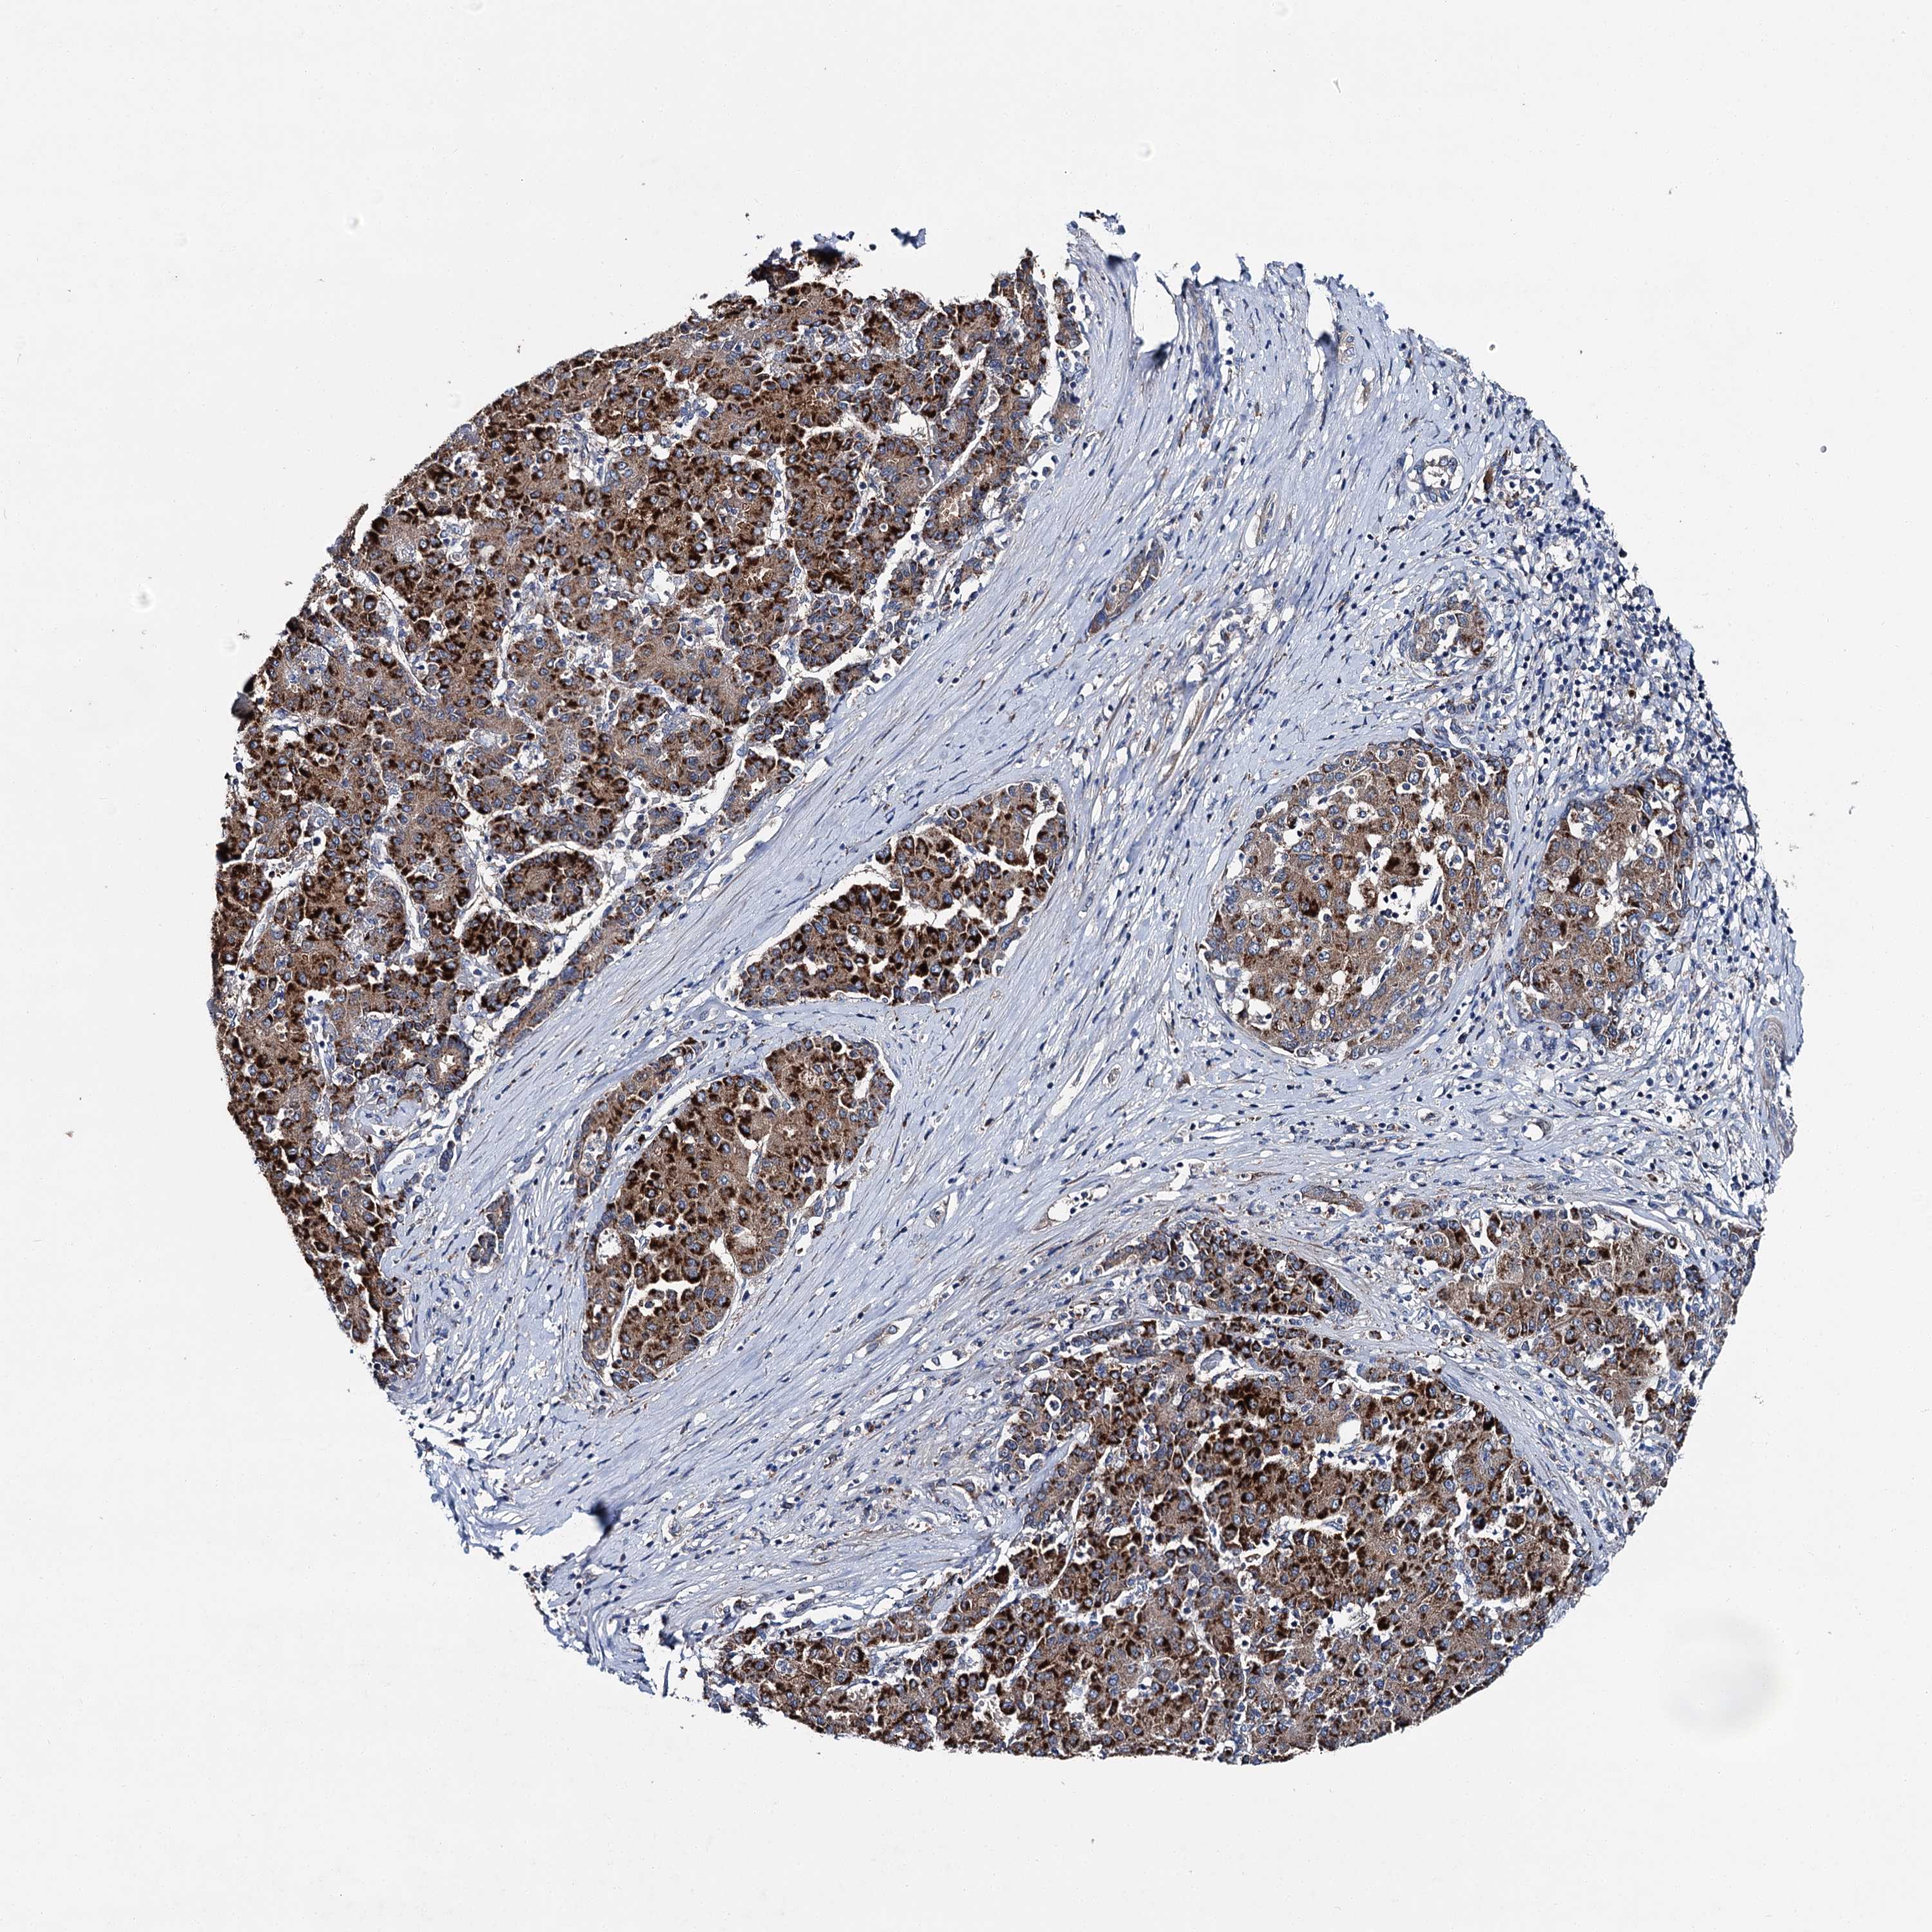

LIVER CANCER - Protein expressioni

A mouse-over function shows sample information and annotation data. Click on an image to view it in a full screen mode. Samples can be filtered based on level of antibody staining by selecting one or several of the following categories: high, medium, low and not detected. The assay and annotation is described here.

Note that samples used for immunohistochemistry by the Human Protein Atlas do not correspond to samples in the TCGA dataset.

Antibody stainingi

Antibody staining in the annotated cell types in the current human tissue is reported as not detected, low, medium, or high, based on conventional immunohistochemistry profiling in selected tissues. This score is based on the combination of the staining intensity and fraction of stained cells.

Each image is clickable and will lead to virtual microscopy that enables deeper exploration of all samples and also displays staining intensity scores, fraction scores and subcellular localization as well as patient and tissue information for each sample.

Antibody HPA039390

Staining

High

Medium

Low

Not detected

Intensity

Strong

Moderate

Weak

Negative

Quantity

>75%

75%-25%

<25%

None

Location

Nuclear

Cytoplasmic/membranous

Cytoplasmic/membranous,nuclear

Cholangiocarcinoma

Carcinoma, Hepatocellular, NOS